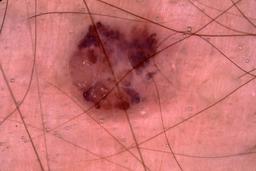

{

"age_approx": 55,

"anatom_site_general": "posterior torso",

"concomitant_biopsy": true,

"dermoscopic_type": "contact non-polarized",

"diagnosis_1": "Malignant",

"diagnosis_2": "Malignant melanocytic proliferations (Melanoma)",

"diagnosis_3": "Melanoma, NOS",

"diagnosis_confirm_type": "histopathology",

"image_type": "dermoscopic",

"lesion_id": "IL_6864076",

"melanocytic": true,

"patient_id": "IP_4659192",

"sex": "female"